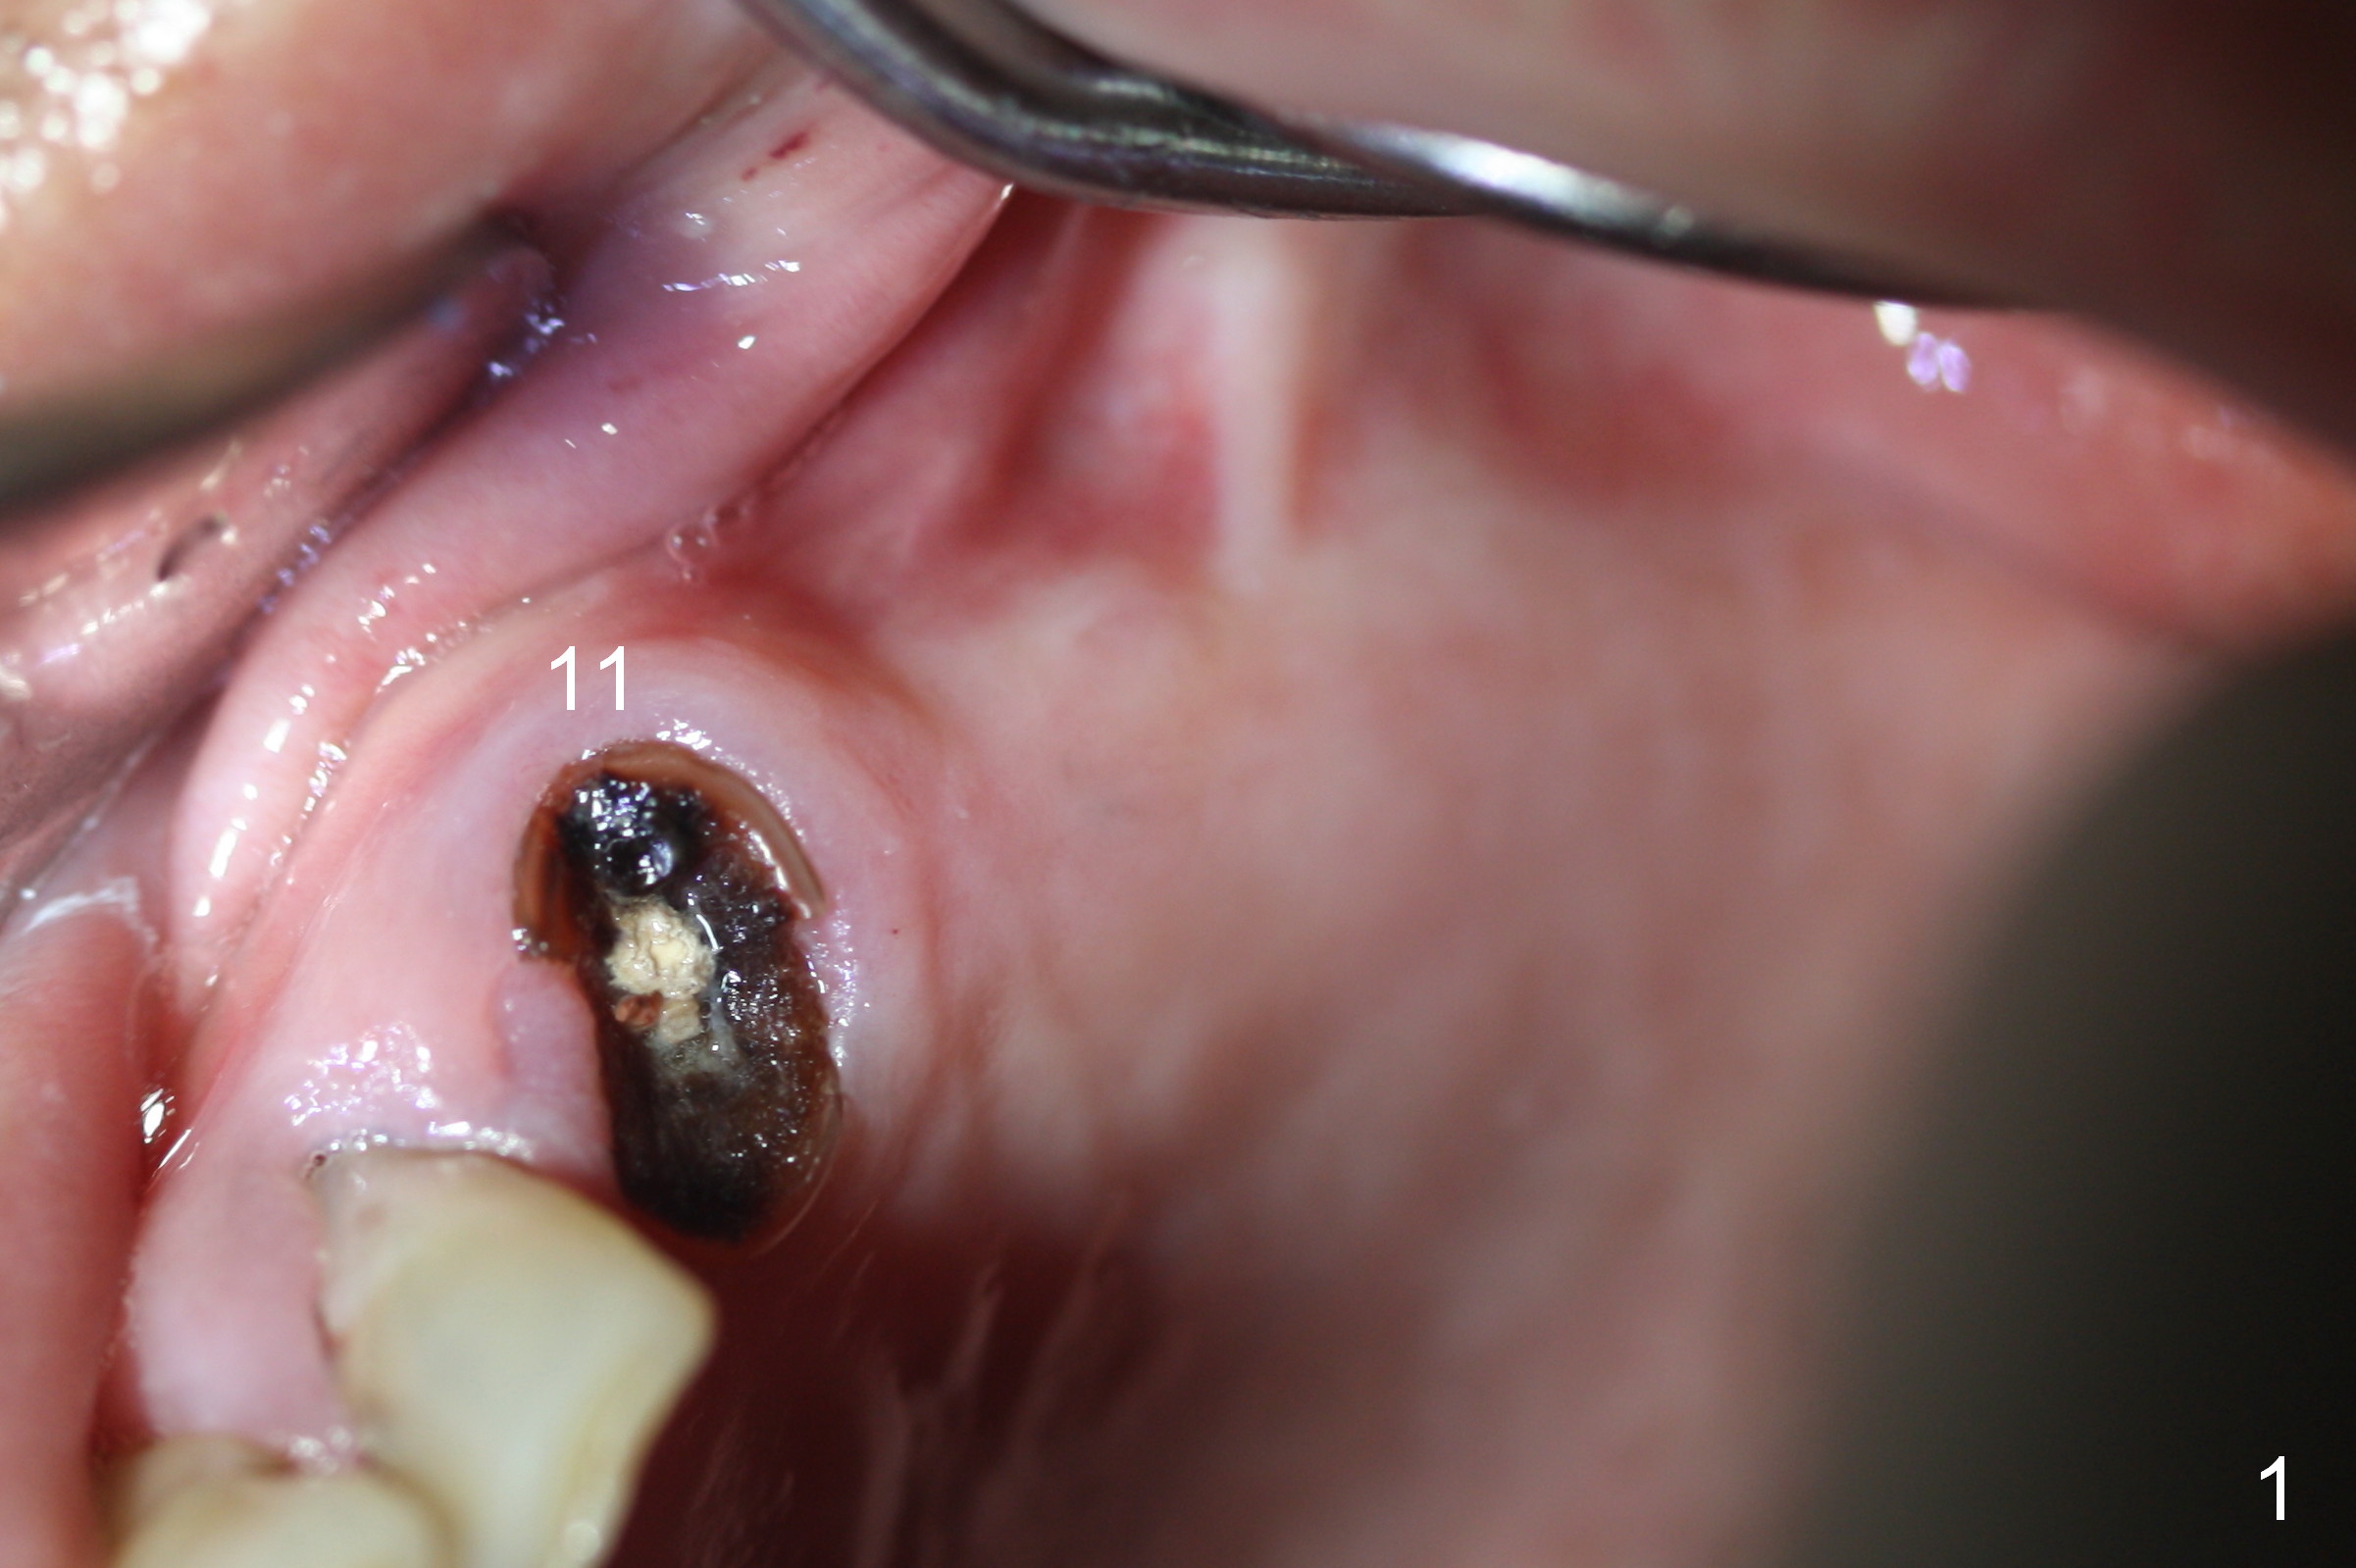

Maxillary Buccal Plate Fracture Due to Bone Expansion

The edentulous ridge distal to #11 residual root is moderately atrophic (Fig.1). The ridge is split with 10 and 13 mm saws between initial osteotomies at #12,14 and 15 (Fig.2). Parallel pins are inserted for trajectory confirmation (Fig.3,4). The gap of the split ridge between #12 and 14 increases when bone expanders (2.7/3.6 mm) are being inserted. A 4.5x17 mm implant does not obtain primary stability at #12. When a 5x17 mm implant is being placed at #12, the buccal plate starts to crack. When the same implant is placed at #14, the crack appears to get larger. Drills are used to finish osteotomy at #14 with force being applied palatally. When the implant is re-inserted, the buccal plate fractures does not appears to get worse (Fig.5 <). In contrast, there is no obvious increase in the gap between #14 and 15 when bone expanders are being used at #15. To avoid complication, drills are used to finish osteotomy before placing a 4.5x14 mm at #15 (Fig.7 (#11: 4.5x17 mm)). CBCT shows that the bone density at #12 and 14 (400-500 Hounsfield units (HU)) is higher than that at #15 (200-300 HU). Ridge split is successful when HU is <200 with smaller diameter implants.